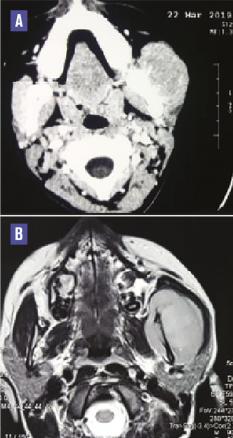

Cette jeune patiente de 14 ans, sans antécédents particuliers, avait depuis 2 mois une tuméfaction de l’angle et de la branche montante de la mandibule sans troubles de la sensibilité labio-mentonnière ni adénopathies cervicales. La tomodensitométrie et l’imagerie par résonance magnétique mandibulaire (fig. 1 ) montraient une ostéolyse mandibulaire avec une importante extension dans les parties molles, surtout du côté lingual, et une réaction périostée spiculée. L’analyse de la biopsie (fig. 2 ) notait une prolifération tumorale constituée de petites cellules rondes exprimant en immunohistochimie le CD99, affirmant le diagnostic de sarcome d’Ewing. Selon le protocole Euro-Ewing 99, chimiothérapie et chirurgie étaient associées, permettant la régression de la tumeur mandibulaire avec, à 6 mois, un contrôle locorégional satisfaisant et l’absence de métastase à distance. La surveillance était maintenue tous les 3 mois.